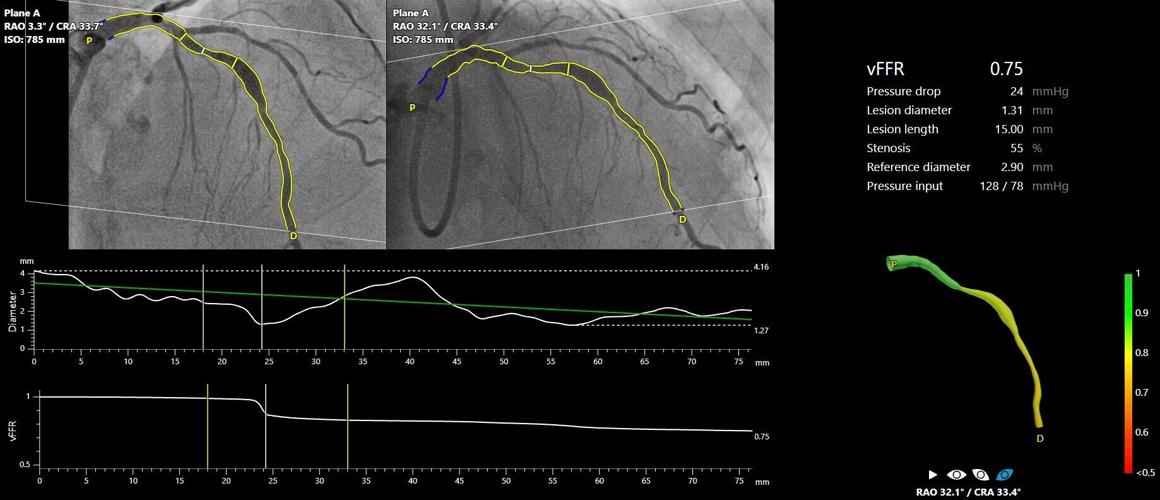

- FAST III was initiated five years ago to evaluate whether revascularization guided by angiography–based FFR using CAAS vFFR (vessel Fractional Flow Reserve) delivers therapeutic outcomes comparable to those achieved with pressure wire–based FFR.

FAST III was an investigator-initiated, open label, multicenter randomized trial comparing vFFR guided versus FFR guided coronary revascularization in 2235 patients with intermediate coronary lesions (defined as 30%-80% stenosis by visual assessment or QCA). Intermediate lesions were physiologically assessed using table side vFFR or FFR and treated if vFFR or FFR ≤0.80. The primary end point was a composite of all-cause death, any myocardial infarction, or any revascularization at 1-year post-randomization.

"The results of FAST III confirm the safety and feasibility of the online use of vFFR as an easy to use minimally invasive tool to guide revascularization in patients with intermediate coronary artery lesions in need of physiological lesion assessment. The technology has the potential to boost the use of physiology, which may increase the prognosis of patients in whom the decision to revascularize intermediate coronary artery lesions is still largely based on eye-balling. The use of vFFR eliminates the need for guiding catheters, invasive coronary artery instrumentation and hyperemic agents with inherent risks and patient discomfort," said Dr. Joost Daemen.